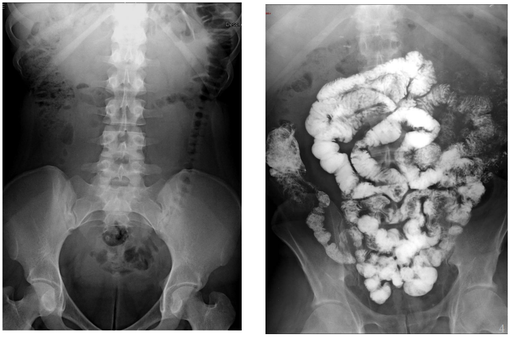

Cancers colo-rectaux

DANSE E. - UCL

Digestif MASTER 1